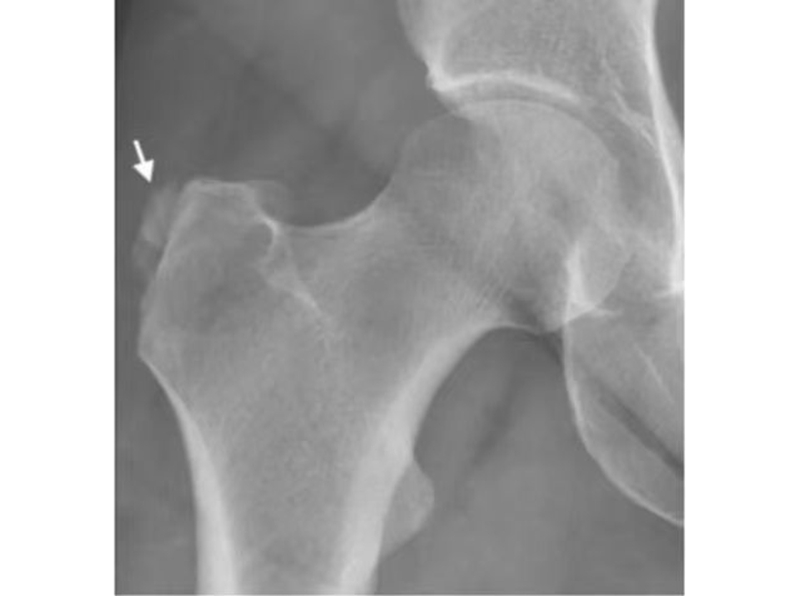

X线和CT可以清晰显示臀肌腱走行区的钙化灶进而提示本病,CT多平面重组图像可用于骨盆各种径线进而排除部分鉴别诊断。骨盆X线检查可以鉴别其他疾病如髋关节退行性疾病、转子撕脱骨折、骨膜肿瘤病变、股骨近端继发性恶性肿瘤等。